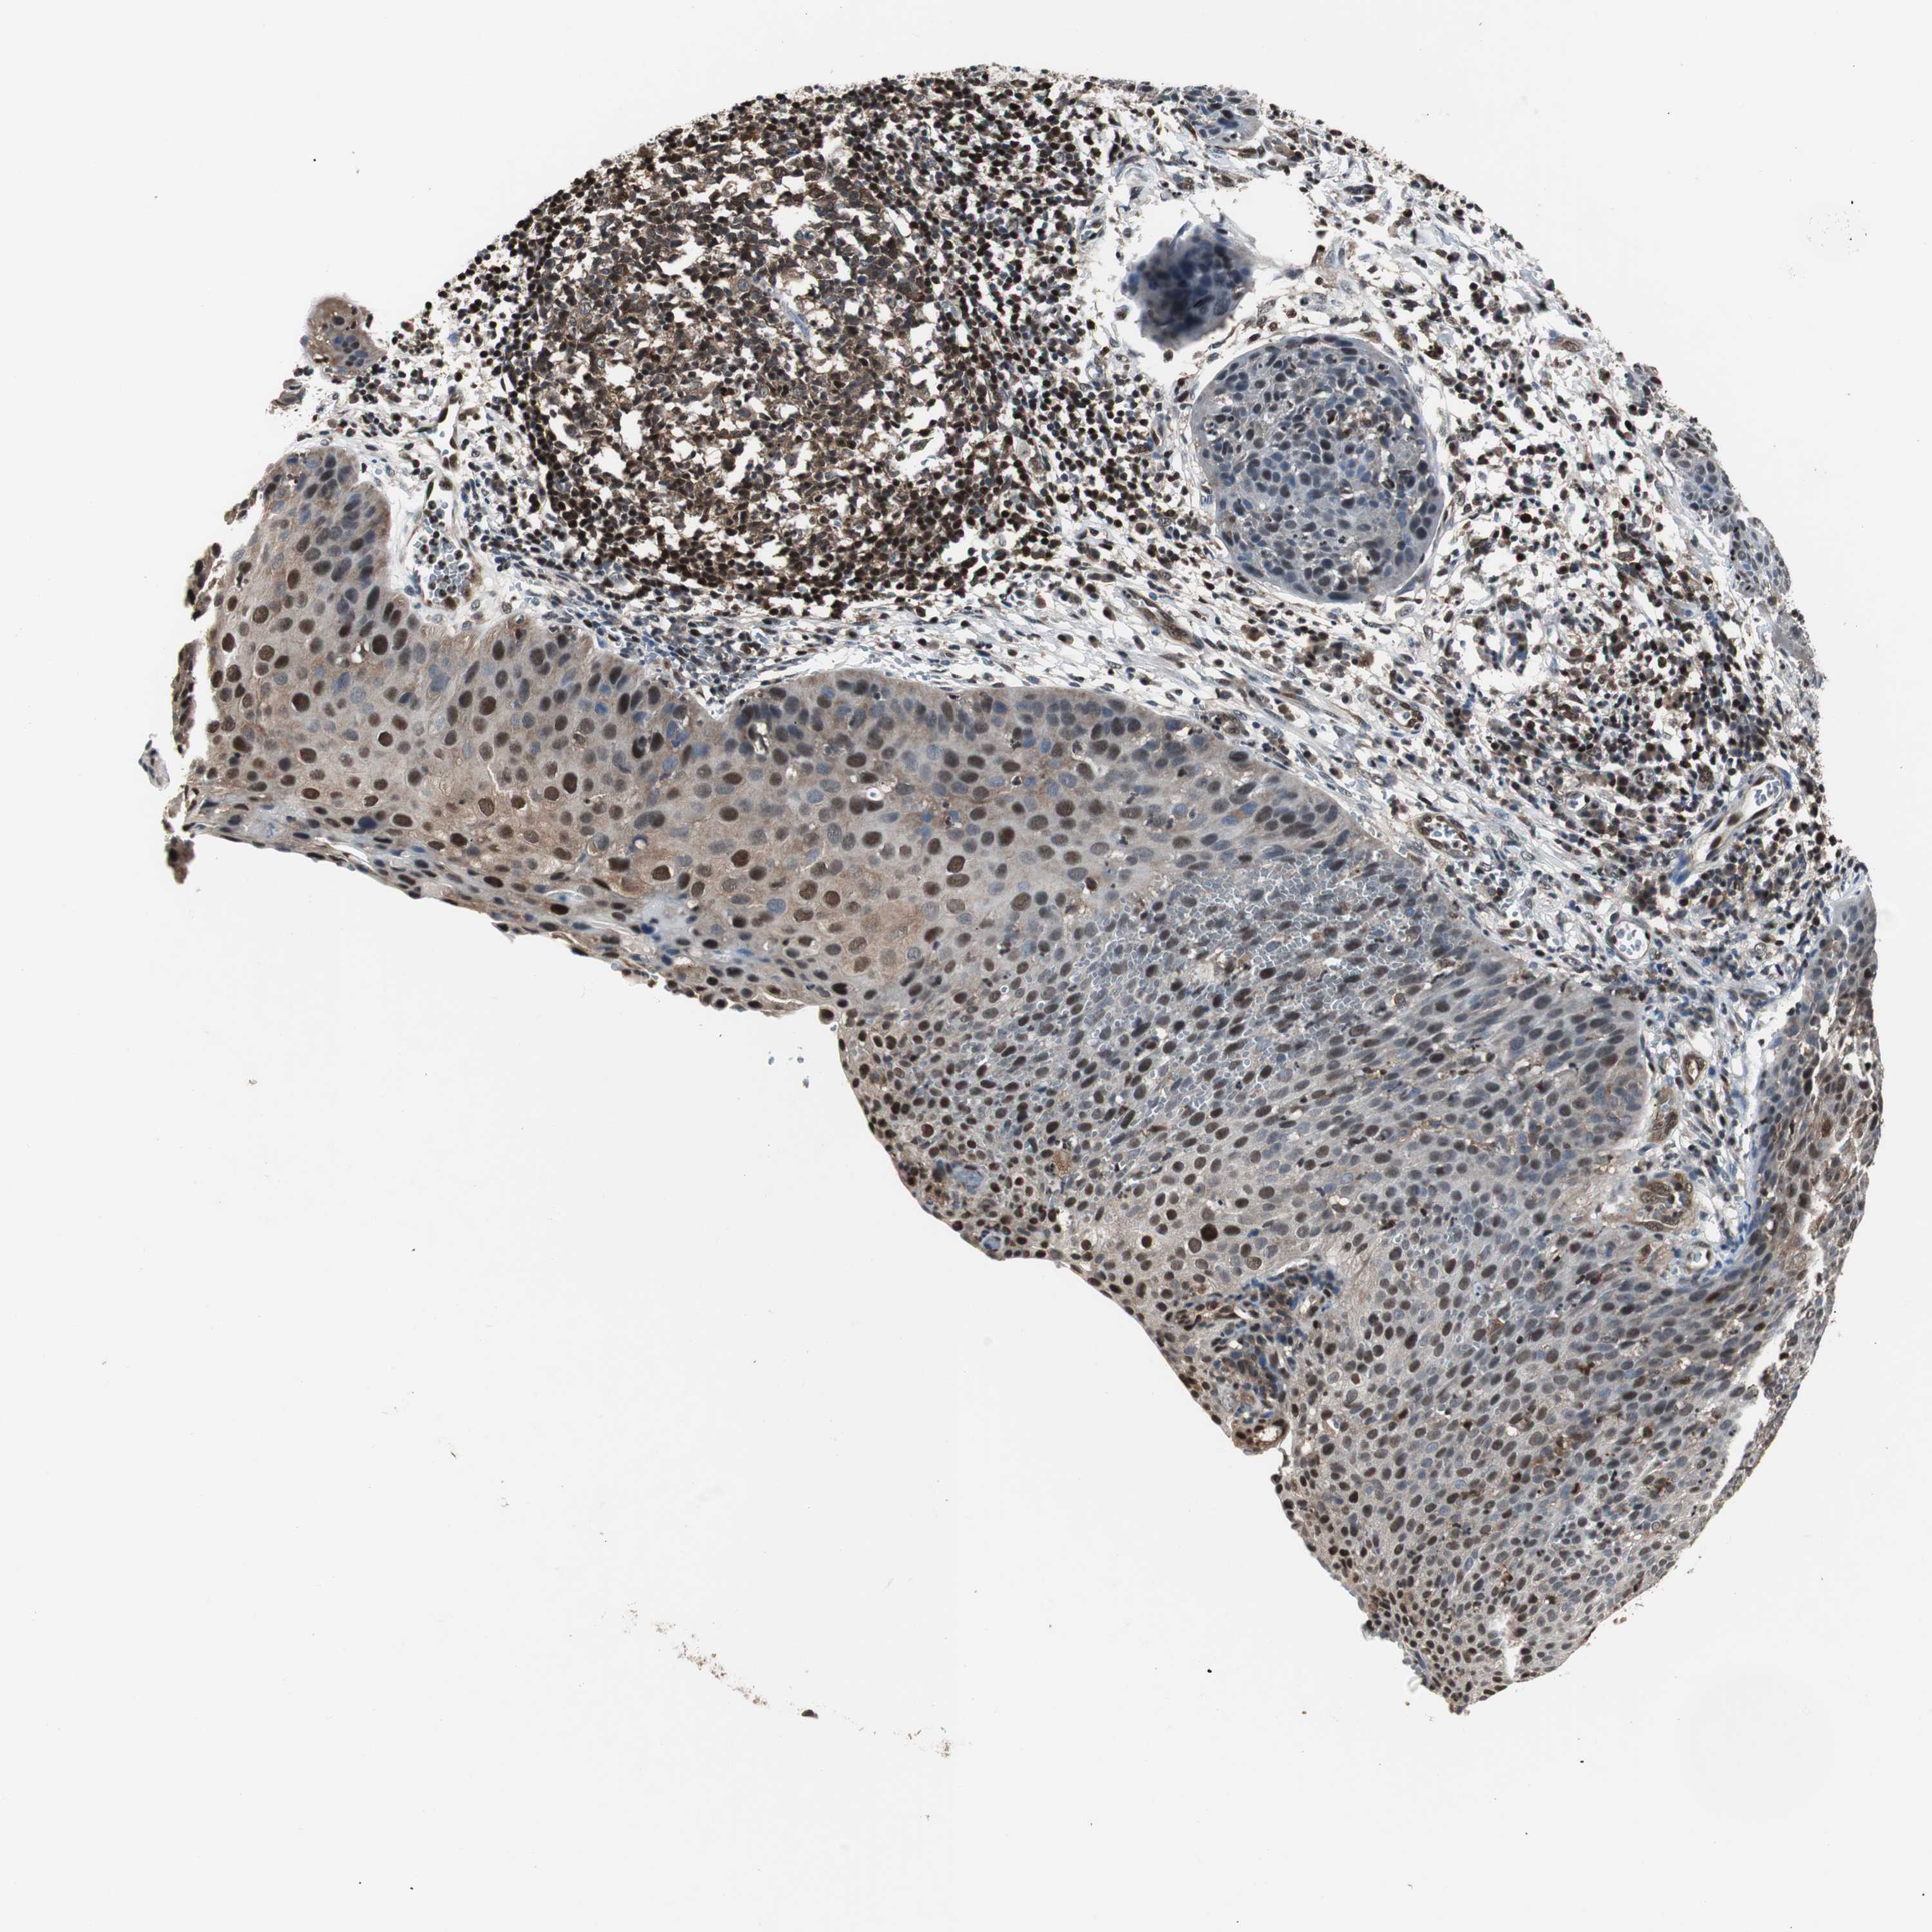

CERVICAL CANCER - Protein expressioni

A mouse-over function shows sample information and annotation data. Click on an image to view it in a full screen mode. Samples can be filtered based on level of antibody staining by selecting one or several of the following categories: high, medium, low and not detected. The assay and annotation is described here.

Note that samples used for immunohistochemistry by the Human Protein Atlas do not correspond to samples in the TCGA dataset.

Antibody stainingi

Antibody staining in the annotated cell types in the current human tissue is reported as not detected, low, medium, or high, based on conventional immunohistochemistry profiling in selected tissues. This score is based on the combination of the staining intensity and fraction of stained cells.

Each image is clickable and will lead to virtual microscopy that enables deeper exploration of all samples and also displays staining intensity scores, fraction scores and subcellular localization as well as patient and tissue information for each sample.

HPA022434

HPA022953

HPA022959

HPA028758

CAB007783

Staining

High

Medium

Low

Not detected

Intensity

Strong

Moderate

Weak

Negative

Quantity

>75%

75%-25%

<25%

None

Location

Nuclear

Cytoplasmic/membranous

Cytoplasmic/membranous,nuclear

Squamous cell carcinoma, NOS

Adenocarcinoma, NOS